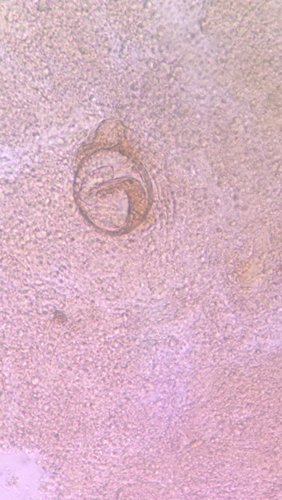

这是寄生虫卵吗?小孩6个月在大便中看到的 点击展开 匿名用户 2013-08-02 14:58 满意回答 不是 匿名用户 2013-08-05 18:41 宝宝知道提示您:回答为网友贡献,仅供参考。 为您推荐: 其他回答 是新趁 匿名用户 2013-08-02 14:59 相关问题 怎样查大便是否有寄生虫呢 宝宝拉便便时有泡沫,过后就没有了,这正常吗?去验大便,检验结果只写黄色浆样便,未见寄生虫 这正常吗 宝宝大便中有黑色长条东西会是寄生虫吗,吃过小米,南瓜,苹果